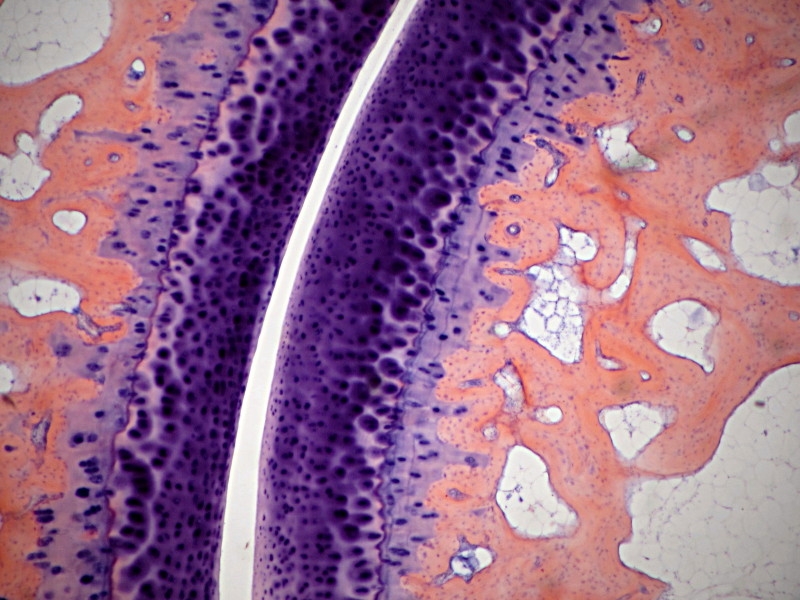

Die Knochenbildung verdeutlicht, mit welcher Erfindungskunst die Natur konstruktive Aufgaben löst: Ein Tragegerüst, das bei voller Funktion noch wächst und zugleich durch Leichtbauweise Raum für Energiespeicher (weißes Knochenmark: Fett) und Regeneration (rotes Knochenmark: Blutbildung) bietet. Ein solches Chassis müssten die Automobilhersteller erst erfinden!

In der Histologie sind Knochenpräparate vielfach vertreten: Längs- und Querschnitte der Knochenbildung, Knorpel und Osteozyten, sowie bei der Haemopoese (Blutbildung).

Hier ein Präparat einer Tibia (Schienbein) eines kleinen Kindes, aus einer Kursserie ca. 1925:

Beschriftung: Tibia, Kind, proximal, in Epiphysennähe. Also in Nähe des Kniegelenks und des Knorpels, der die Gelenkfläche bildet.

Gefärbt wurde mit Haematoxylin und Rosindulin. Man erkennt das lockere Gerüst der Knochenbälkchen (gelb-rosa) und dazwischen die Zellen des Roten Knochenmarks, dessen Bau und Funktion in einem früheren Faden sehr schön beschrieben wurde: https://www.mikroskopie-forum.de/index.php?topic=3785.0.